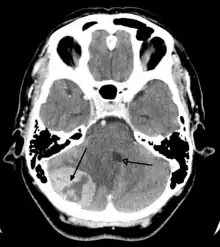

Imaging

Medical imaging plays a central role in the diagnosis of brain tumors. Early imaging methods – invasive and sometimes dangerous – such as pneumoencephalography and cerebral angiography have been abandoned in favor of non-invasive, high-resolution techniques, especially magnetic resonance imaging (MRI) and computed tomography (CT) scans,[38] though MRI is typically the reference standard used.[41] Neoplasms will often show as differently colored masses (also referred to as processes) in CT or MRI results.

- Benign brain tumors often show up as hypodense (darker than brain tissue) mass lesions on CT scans. On MRI, they appear either hypodense or isointense (same intensity as brain tissue) on T1-weighted scans, or hyperintense (brighter than brain tissue) on T2-weighted MRI, although the appearance is variable.

- Contrast agent uptake, sometimes in characteristic patterns, can be demonstrated on either CT or MRI scans in most malignant primary and metastatic brain tumors.

- Pressure areas where the brain tissue has been compressed by a tumor also appear hyperintense on T2-weighted scans and might indicate the presence of a diffuse neoplasm due to an unclear outline. Swelling around the tumor known as peritumoral edema can also show a similar result. This is because these tumors disrupt the normal functioning of the BBB and lead to an increase in its permeability.

Computed Tomography (CT) Scan- uses x-rays to take pictures from different angles and computer processing to combine the pictures into a 3D image. A CT scan usually serves as an alternative to MRI in cases where the patient cannot have an MRI due to claustrophobia or pacemaker. Compared to MRI, a CT scan shows a more detailed image of the bone structures near the tumor and can be used to measure the tumor’s size.[48] Like an MRI, a contrast dye may also be injected into the veins or ingested by mouth before a CT scan to better outline any tumors that may be present. CT scans use contrast materials that are iodine-based and barium sulfate compounds. The downside of using CT scans as opposed to MRI is that some brain tumors do not show up well on CT scans because some intra-axial masses are faint and resemble normal brain tissue. In some scenarios, brain tumors in CT scans may be mistaken for infarction, infection, and demyelination. To suspect that an intra-axial mass is a brain tumor instead of other possibilities, there must be unexplained calcifications in the brain, preservation of the cortex, and disproportionate mass effect.[49]